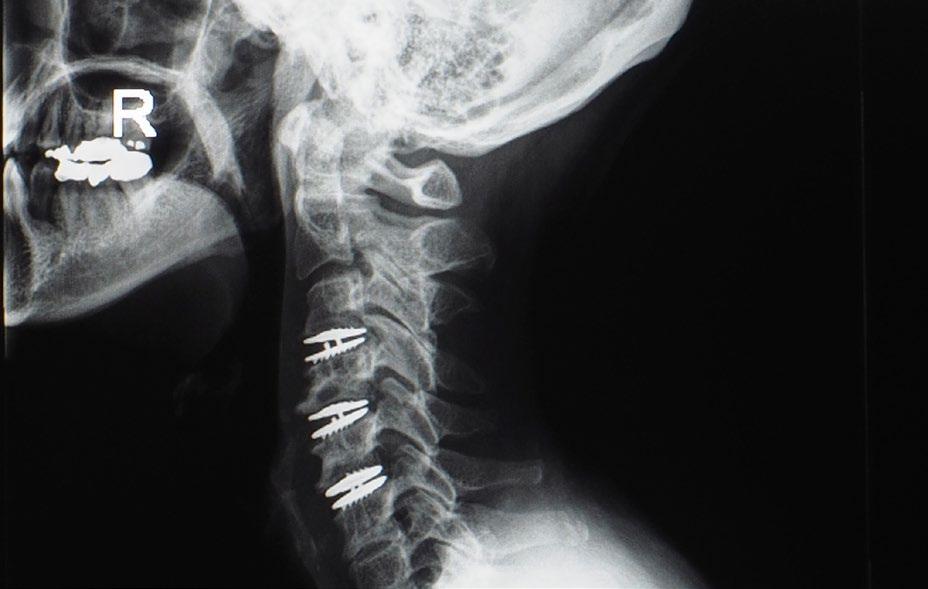

Updates on Biomechanics of Cervical Disc Arthroplasty

Anterior cervical discectomy and fusion has historically been considered the gold standard for neural decompression and disc height restoration among patients with cervical spondylosis who have exhausted conservative measures.1 In recent years, however, the aging population and growing focus on value-based treatment spurred the advent of motion-sparing technologies. Cervical disc arthroplasty (CDA) was developed as a means of preserving physiologic biomechanics and mitigating the shortcomings of traditional fusion (namely, adjacent segment degeneration, restriction of motion, and long-term cost effectiveness). 2

The US Food and Drug Administration (FDA) has thus far approved 9 artificial discs (Prestige ST, Prodisc-C, Bryan, Secure-C, PCM, Mobi-C, Prestige LP, M6-C, and Simplify) for single-level arthroplasty and 2 artificial discs (Mobi-C and Prestige LP) for 2-level arthroplasty. 3 CDA has subsequently garnered extensive level I and II evidence supporting its use and is now considered an important technique in the spine surgeon’s armamentarium. Despite its safety and efficacy, however, CDA requires meticulous technical proficiency and preoperative planning. Implant-specific variables such as the

degree of constraint, number of components, type of articulation, material composition, and endplate surface constructs largely influence postoperative functionality and kinematics.4,5 As such, a thorough understanding of implant design is critical to optimize device selection, spinal biomechanics, and patient outcomes.